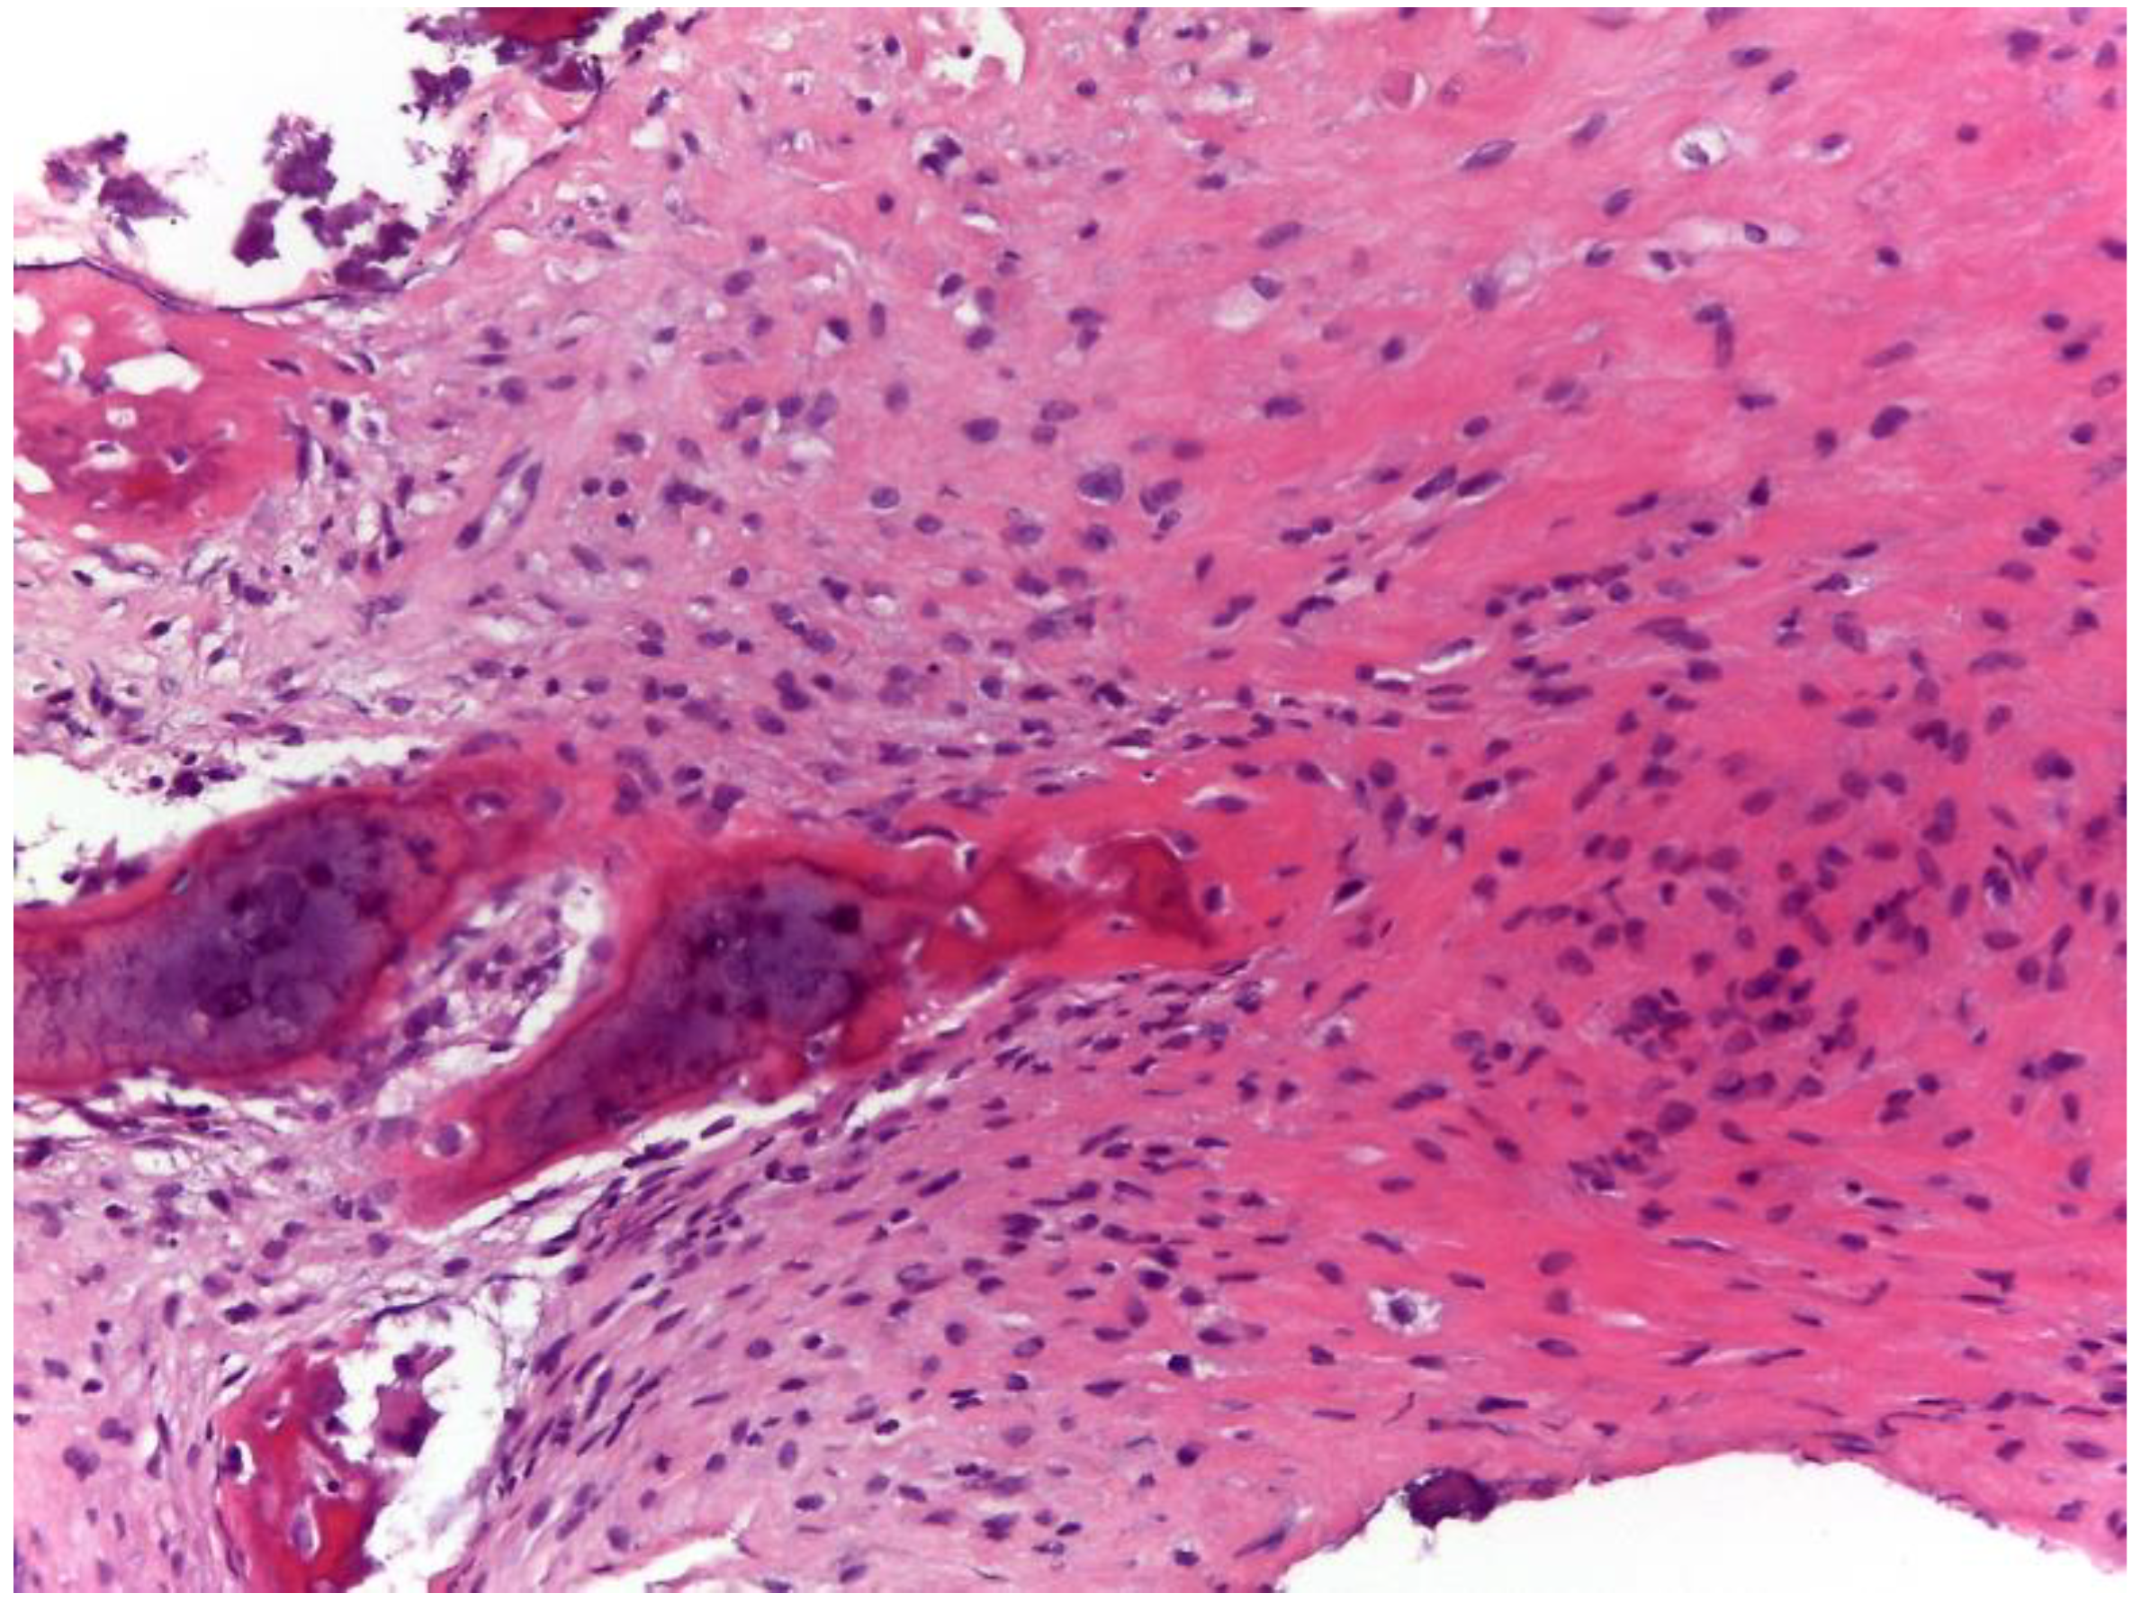

2.1. Oncological Staging